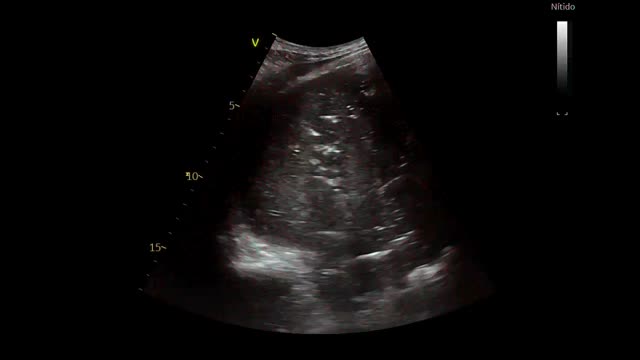

An anteroposterior chest radiography showed an area of lung consolidation in lower right lobe, indicating pneumonia (see Fig. 1). The lung ultrasound showed lobar consolidation, air bronchogram, pleural effusion and fibrin (see Fig. 2), as well as hyperechoic opacities that move centrifugally with respiration (dynamic air bronchogram) (see suppl. material 1). The patient was discharged alive after 2 months.